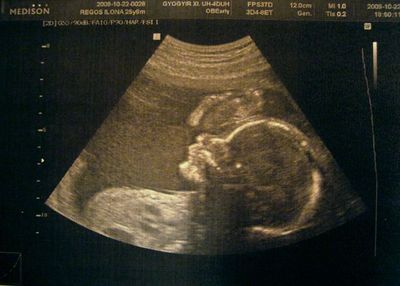

Akkor a 20 hetes pocakok.

19+5

20+0